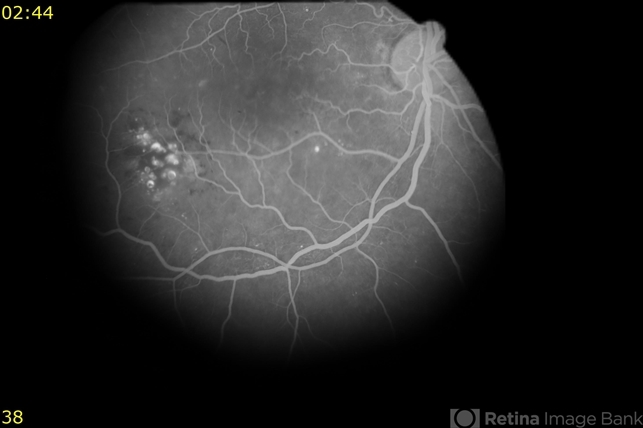

- Cavernous Hemangioma of the Retina

- 54-year-old sent in with CME and Dx of BVO. She was 20/70. She did not have a diagnosis of diabetes at the time, but FA finding suggestive of DR, so will get her tested via her PCP. There is a cluster of saccular aneurysms infero-temporally that show some hyperFL of the top of the aneurysm.